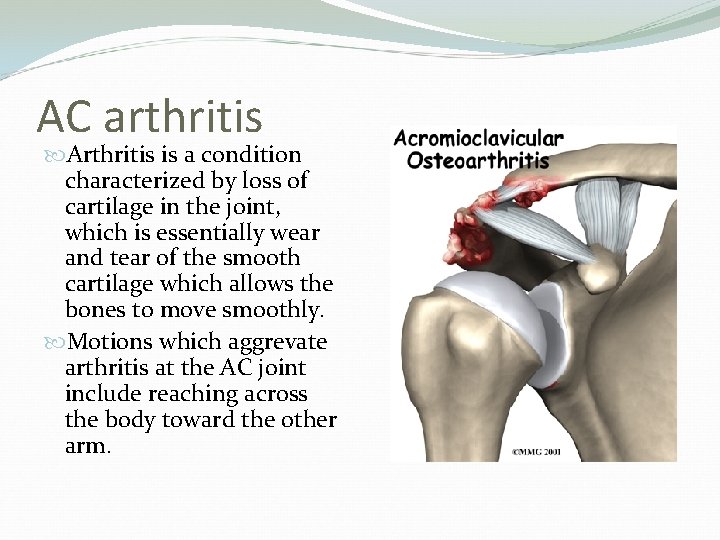

AC arthritis Arthritis is a condition characterized by loss of cartilage in the joint, which is essentially wear and tear of the smooth cartilage which allows the bones to move smoothly. Motions which aggrevate arthritis at the AC joint include reaching across the body toward the other arm.

Signs and Symptoms Pain , which worsens with movement and progressively worsens. ( the patient may suffer a night pain which is a sign of arthritis) It is commonly associated with impingement syndrome Diagnosis: Clinical and by x-rays